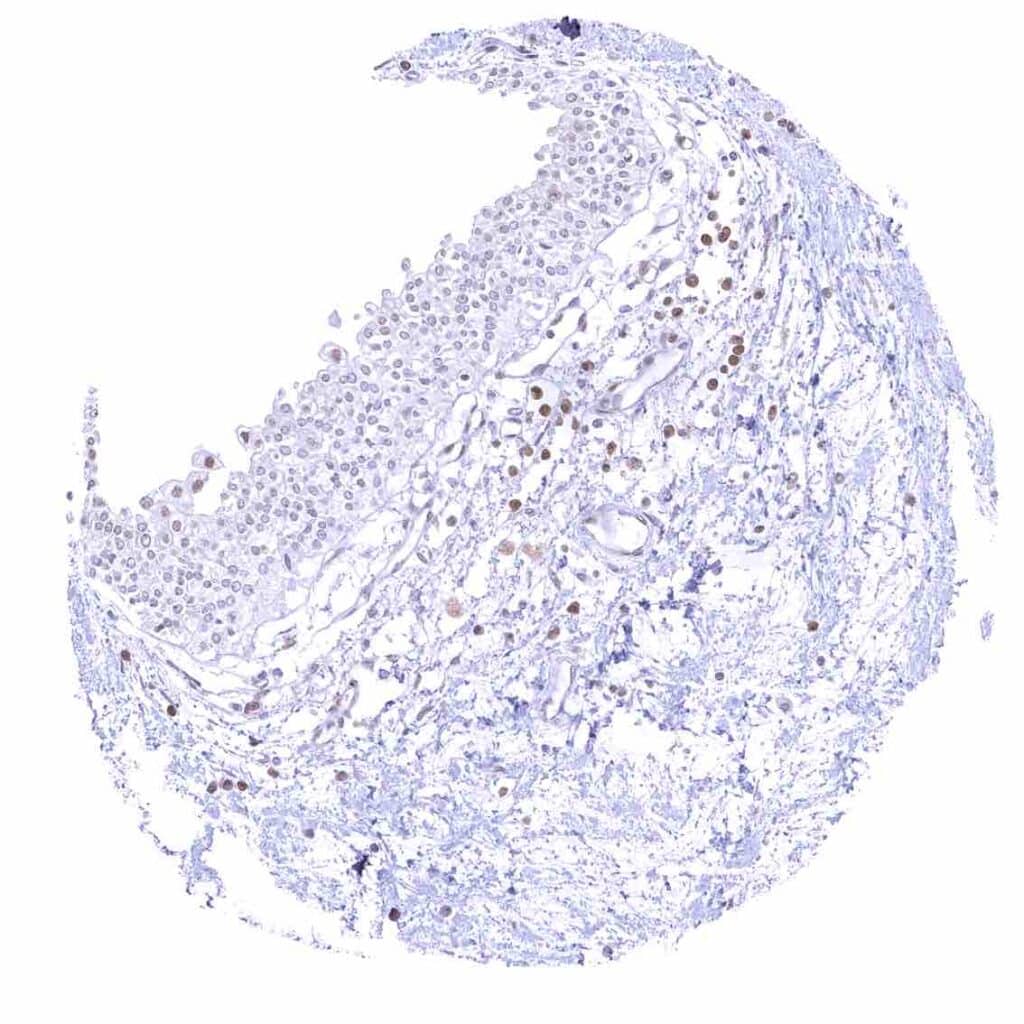

Skin – Moderate to strong nuclear p27 staining occurs in a large fraction of squamous epithelial cells and predominates in the more mature cell layers (top 50_ of the epidermis).